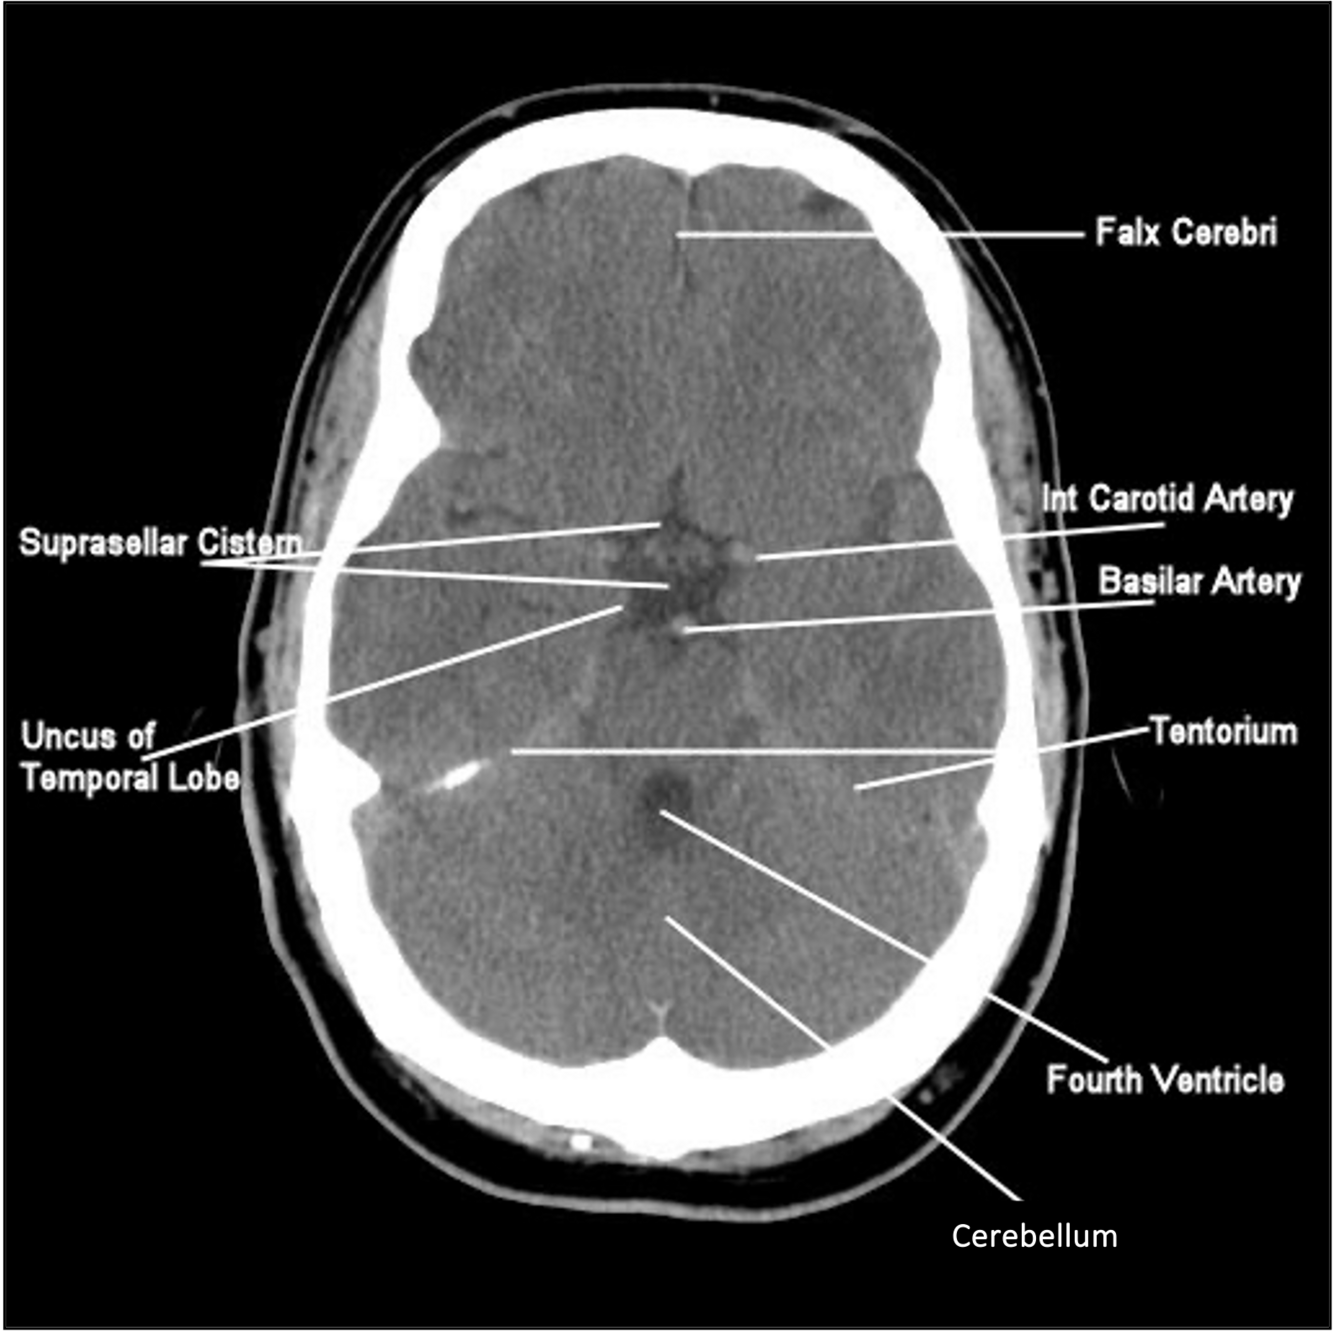

What is the suprasellar cistem ?

Suprasellar cistern is star shaped

Sella turcica is below it

Sella turcica (where pituitary gland sits)

Suprasellar cistern—where the circle of willis sits

Common site for aneurysm, with rupture will see blood in this space (subarachnoid)

What is falx cerebri

Dura that separating the two hemispheres